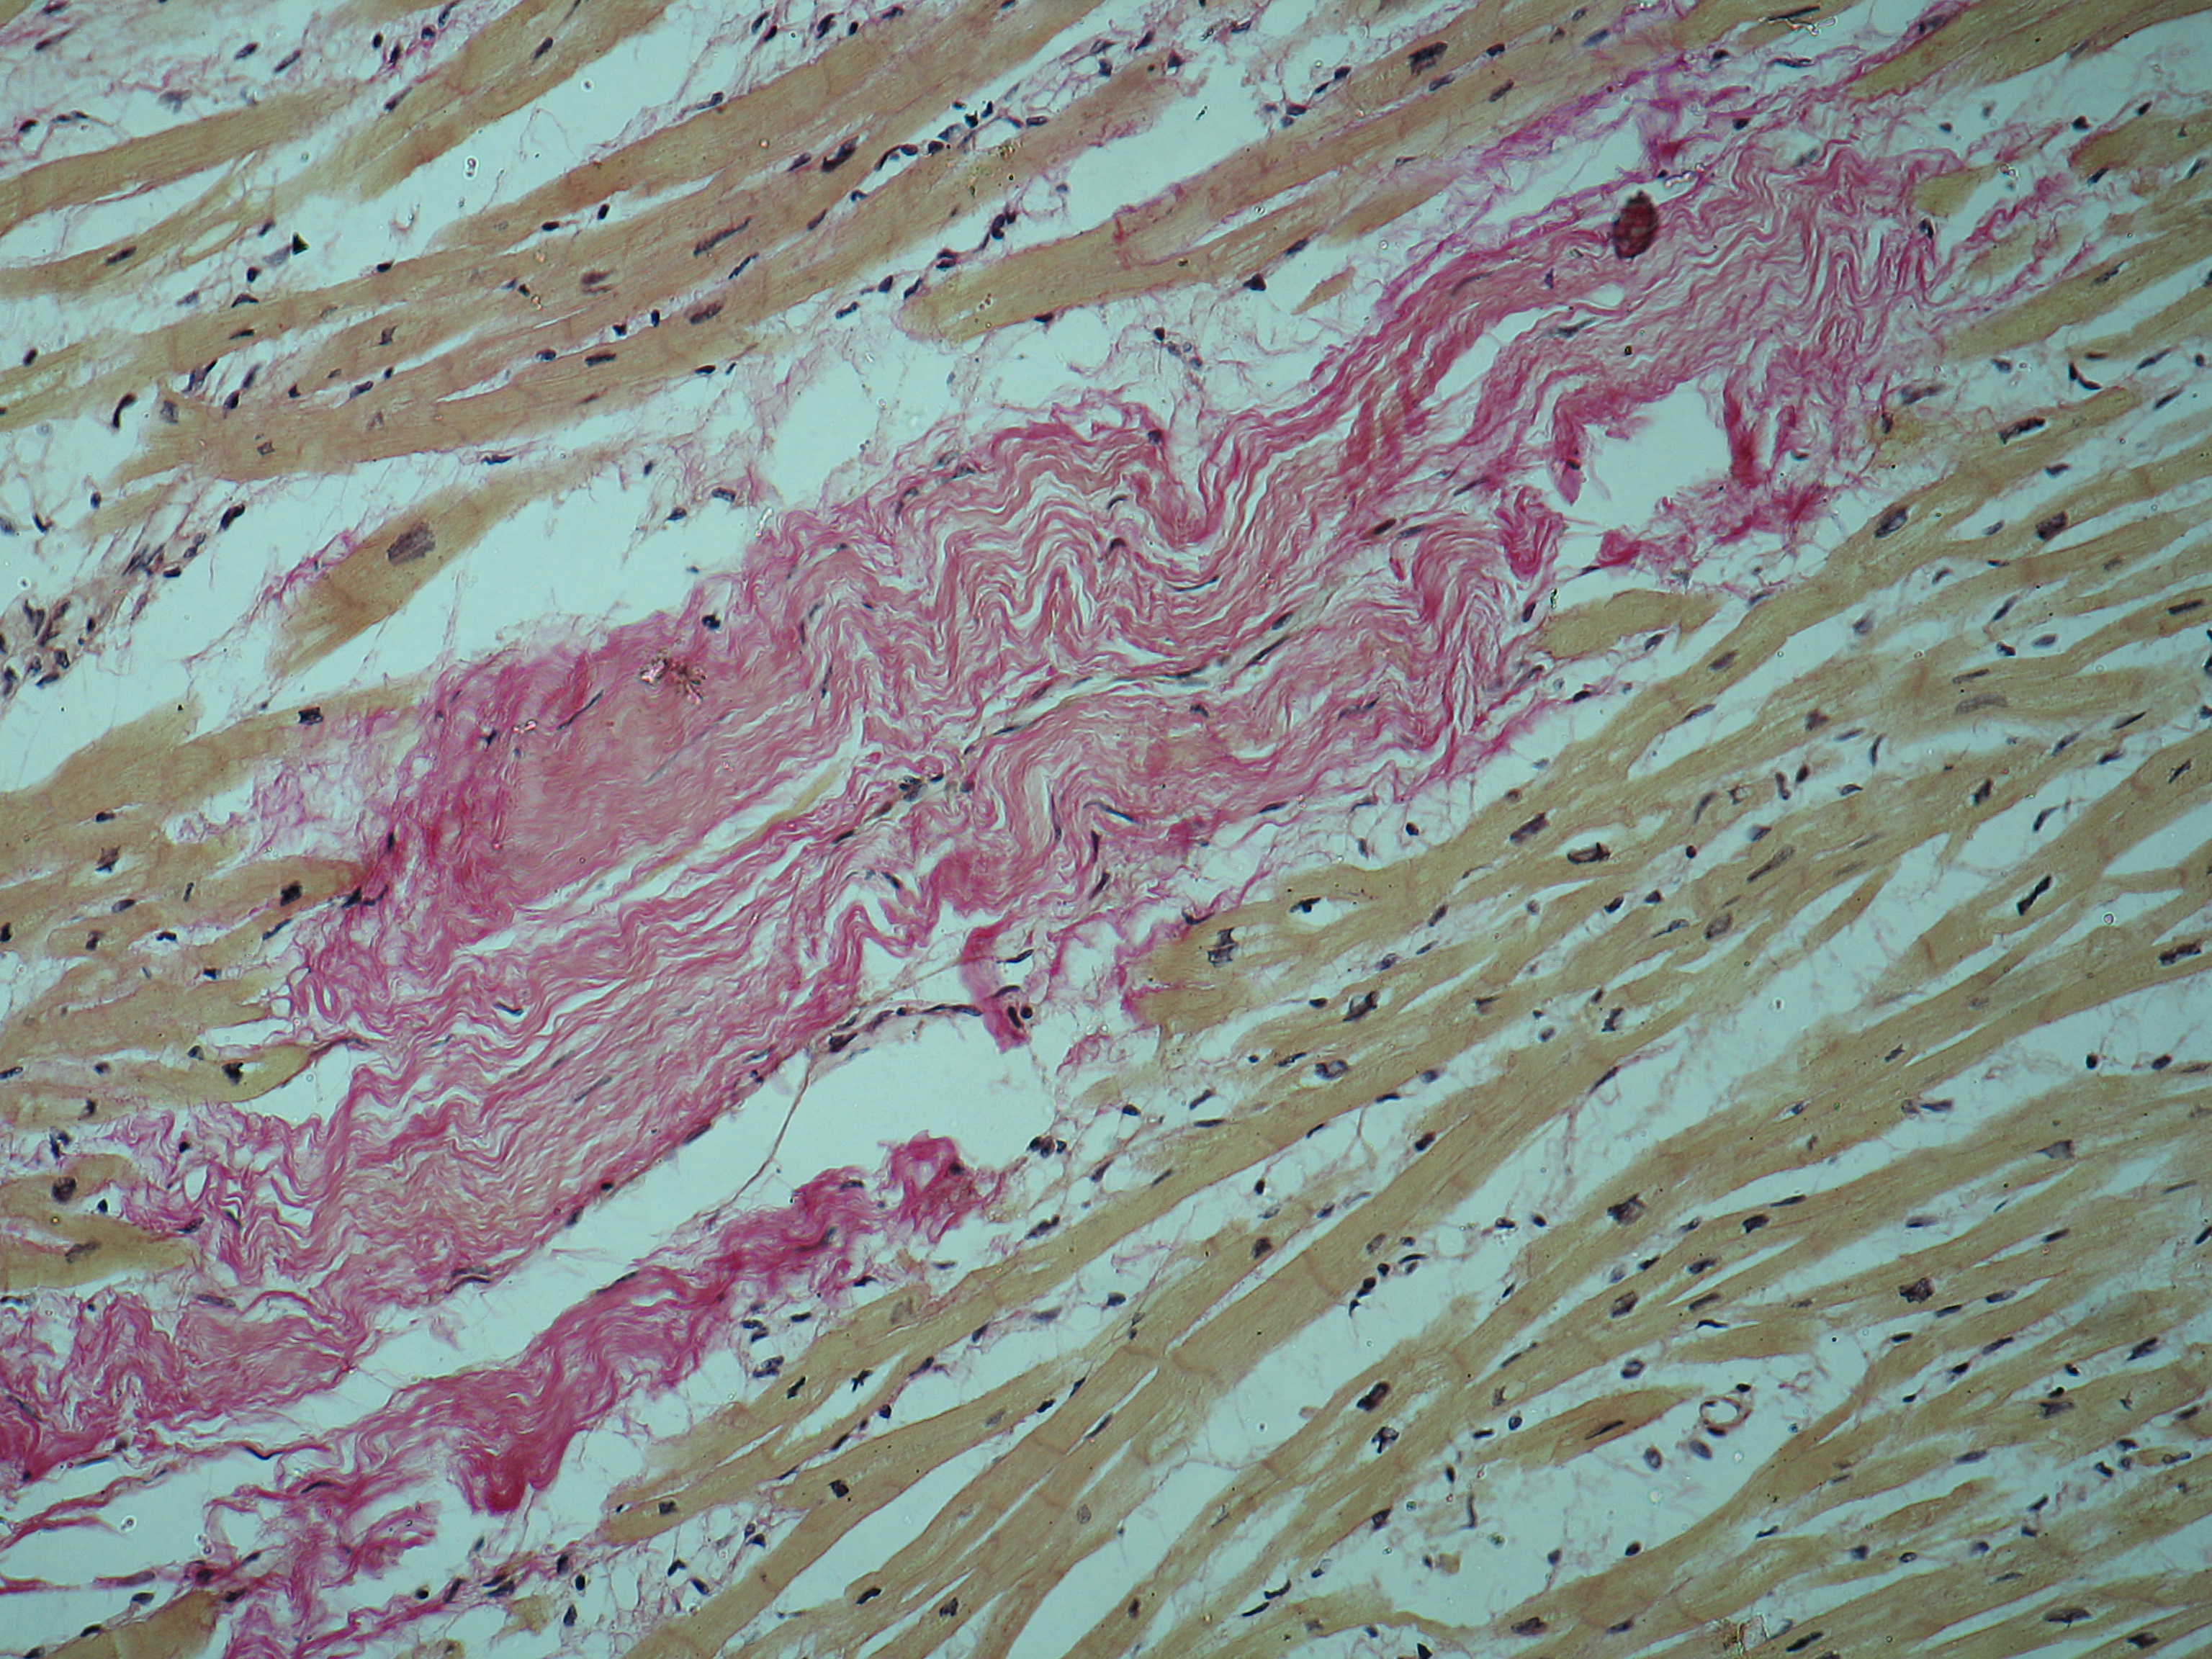

Межуточный миокардит: гистологические исследования

Раздел: Идеи и советы